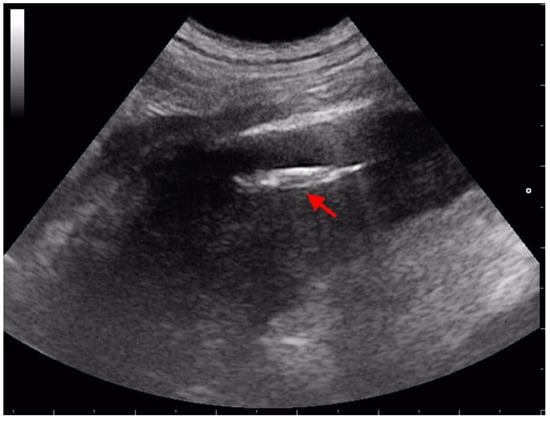

3.2. Retroperitoneal Migration